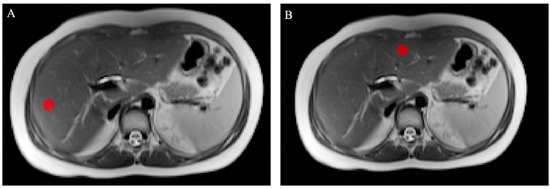

3.2. Magnetic Resonance Imaging